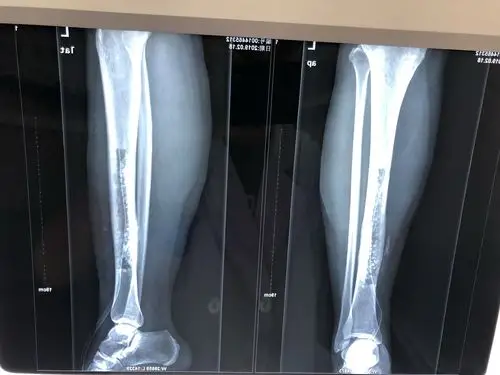

慢性骨髓炎

慢性骨髓炎伴骨外漏

这一例胫骨慢性骨髓炎大家有啥好建议

20多年慢性骨髓炎,求助 [病例帖]

女,32岁,右内踝骨髓炎